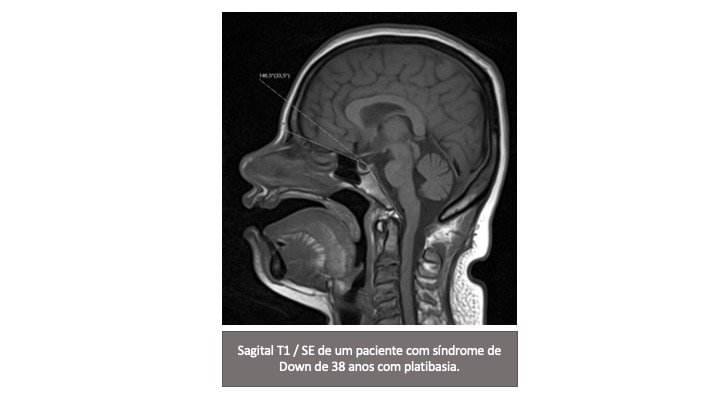

Por fim, a SD está associada ao achatamento da base do crânio ou platibasia, que se reflete no aumento do ângulo da base do crânio (FIGURA 2). Este ângulo é medido usando uma linha que une o násio com o centro da fossa pituitária e uma linha que une a borda anterior do forame magno e o centro da fossa pituitária. Um ângulo superior a 143 ° define a platibasia.